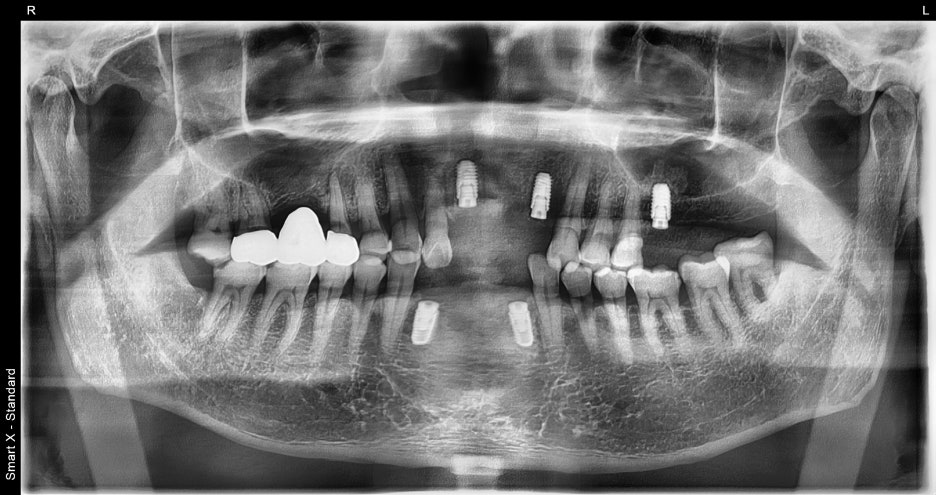

③ Implant placement (5 in total)

– Five implants were placed in multiple areas.

– In some areas, the bone thickness was insufficient,

so bone grafting (allograft) was performed together.

– Using digital equipment, the implants were placed at precise positions and angles,

securing both aesthetics and function.